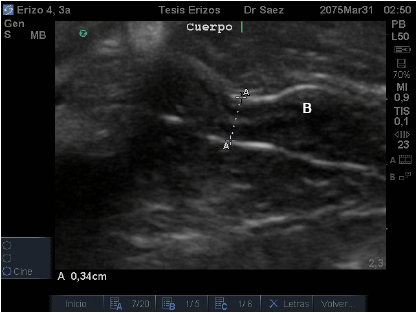

Craneal al cérvix se observó la continuación de una estructura tubular de menor diámetro y ligeramente hiperecoica en relación al cérvix e isoecoica con la vagina media y, al igual que ésta, en algunas ocasiones, se visualizó una banda hiperecoica en su interior, una banda media hipoecoica y una banda hiperecoica externamente (FIG. 3). Desde allí nacen ambos cuernos uterinos, por lo que este segmento correspondería al cuerpo uterino. Algunos autores indican, que las hembras de erizo de tierra africano no poseen cuerpo uterino [2, 6, 10], lo que se contradice con los resultados obtenidos en este estudio, Sería muy importante realizar un estudio anatómico, acompañado de muestras histológicas para verificar estos resultados.

Los cuernos uterinos se visualizaron como estructuras tubulares, hipoecoicas, homogéneas, de granulado fino, naciendo desde el cuerpo uterino y dirigiéndose cráneo-lateral para luego girar caudo-lateral. En algunos individuos, fue visible una banda hiperecoica en su interior, al igual que en la vagina y cuerpo uterino.